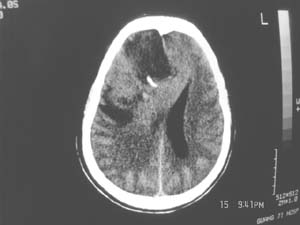

女,60岁,反复头痛3天,呕吐3小时伴昏迷10分钟入院检查。

右额叶占位,有占位效应,中线偏移,病灶位于镰旁,呈囊实性并有钙化,

考虑:1.脑膜瘤。2.胶质瘤。

理由:1.病灶位于前颅凹及镰旁,有明显占位效应---支持脑膜瘤。

2.病灶呈囊实质性并有条状钙化,符合胶质瘤改变;

另外也不排除包虫病的可能。

右额叶占位,有占位效应,中线偏移,病灶位于镰旁,呈囊实性并有钙化 kaolv  少枝胶质瘤。胶质瘤。

结合病史这么短,病情进展迅速,从常见病多发病方面考虑,比较符合脑血管病,故首先考虑出血性脑梗塞;

其次考虑脑肿瘤,是否并有瘤卒中,还是钙化我觉得ct值很重要;

病变范围较大,累及左额叶,内见钙化。及高密度灶。考虑;胶母伴卒中可能大。